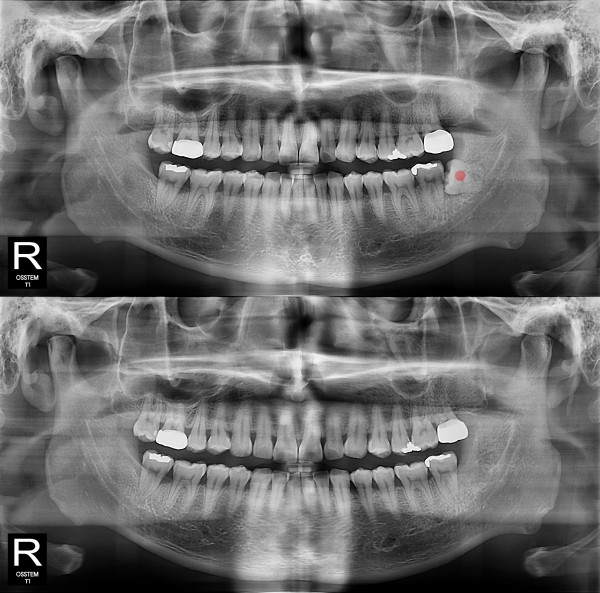

智齿拔除 完全埋伏智齿

b047bd763797d0ee5fe0c71c12970e9f_1766119523_1671.jpg